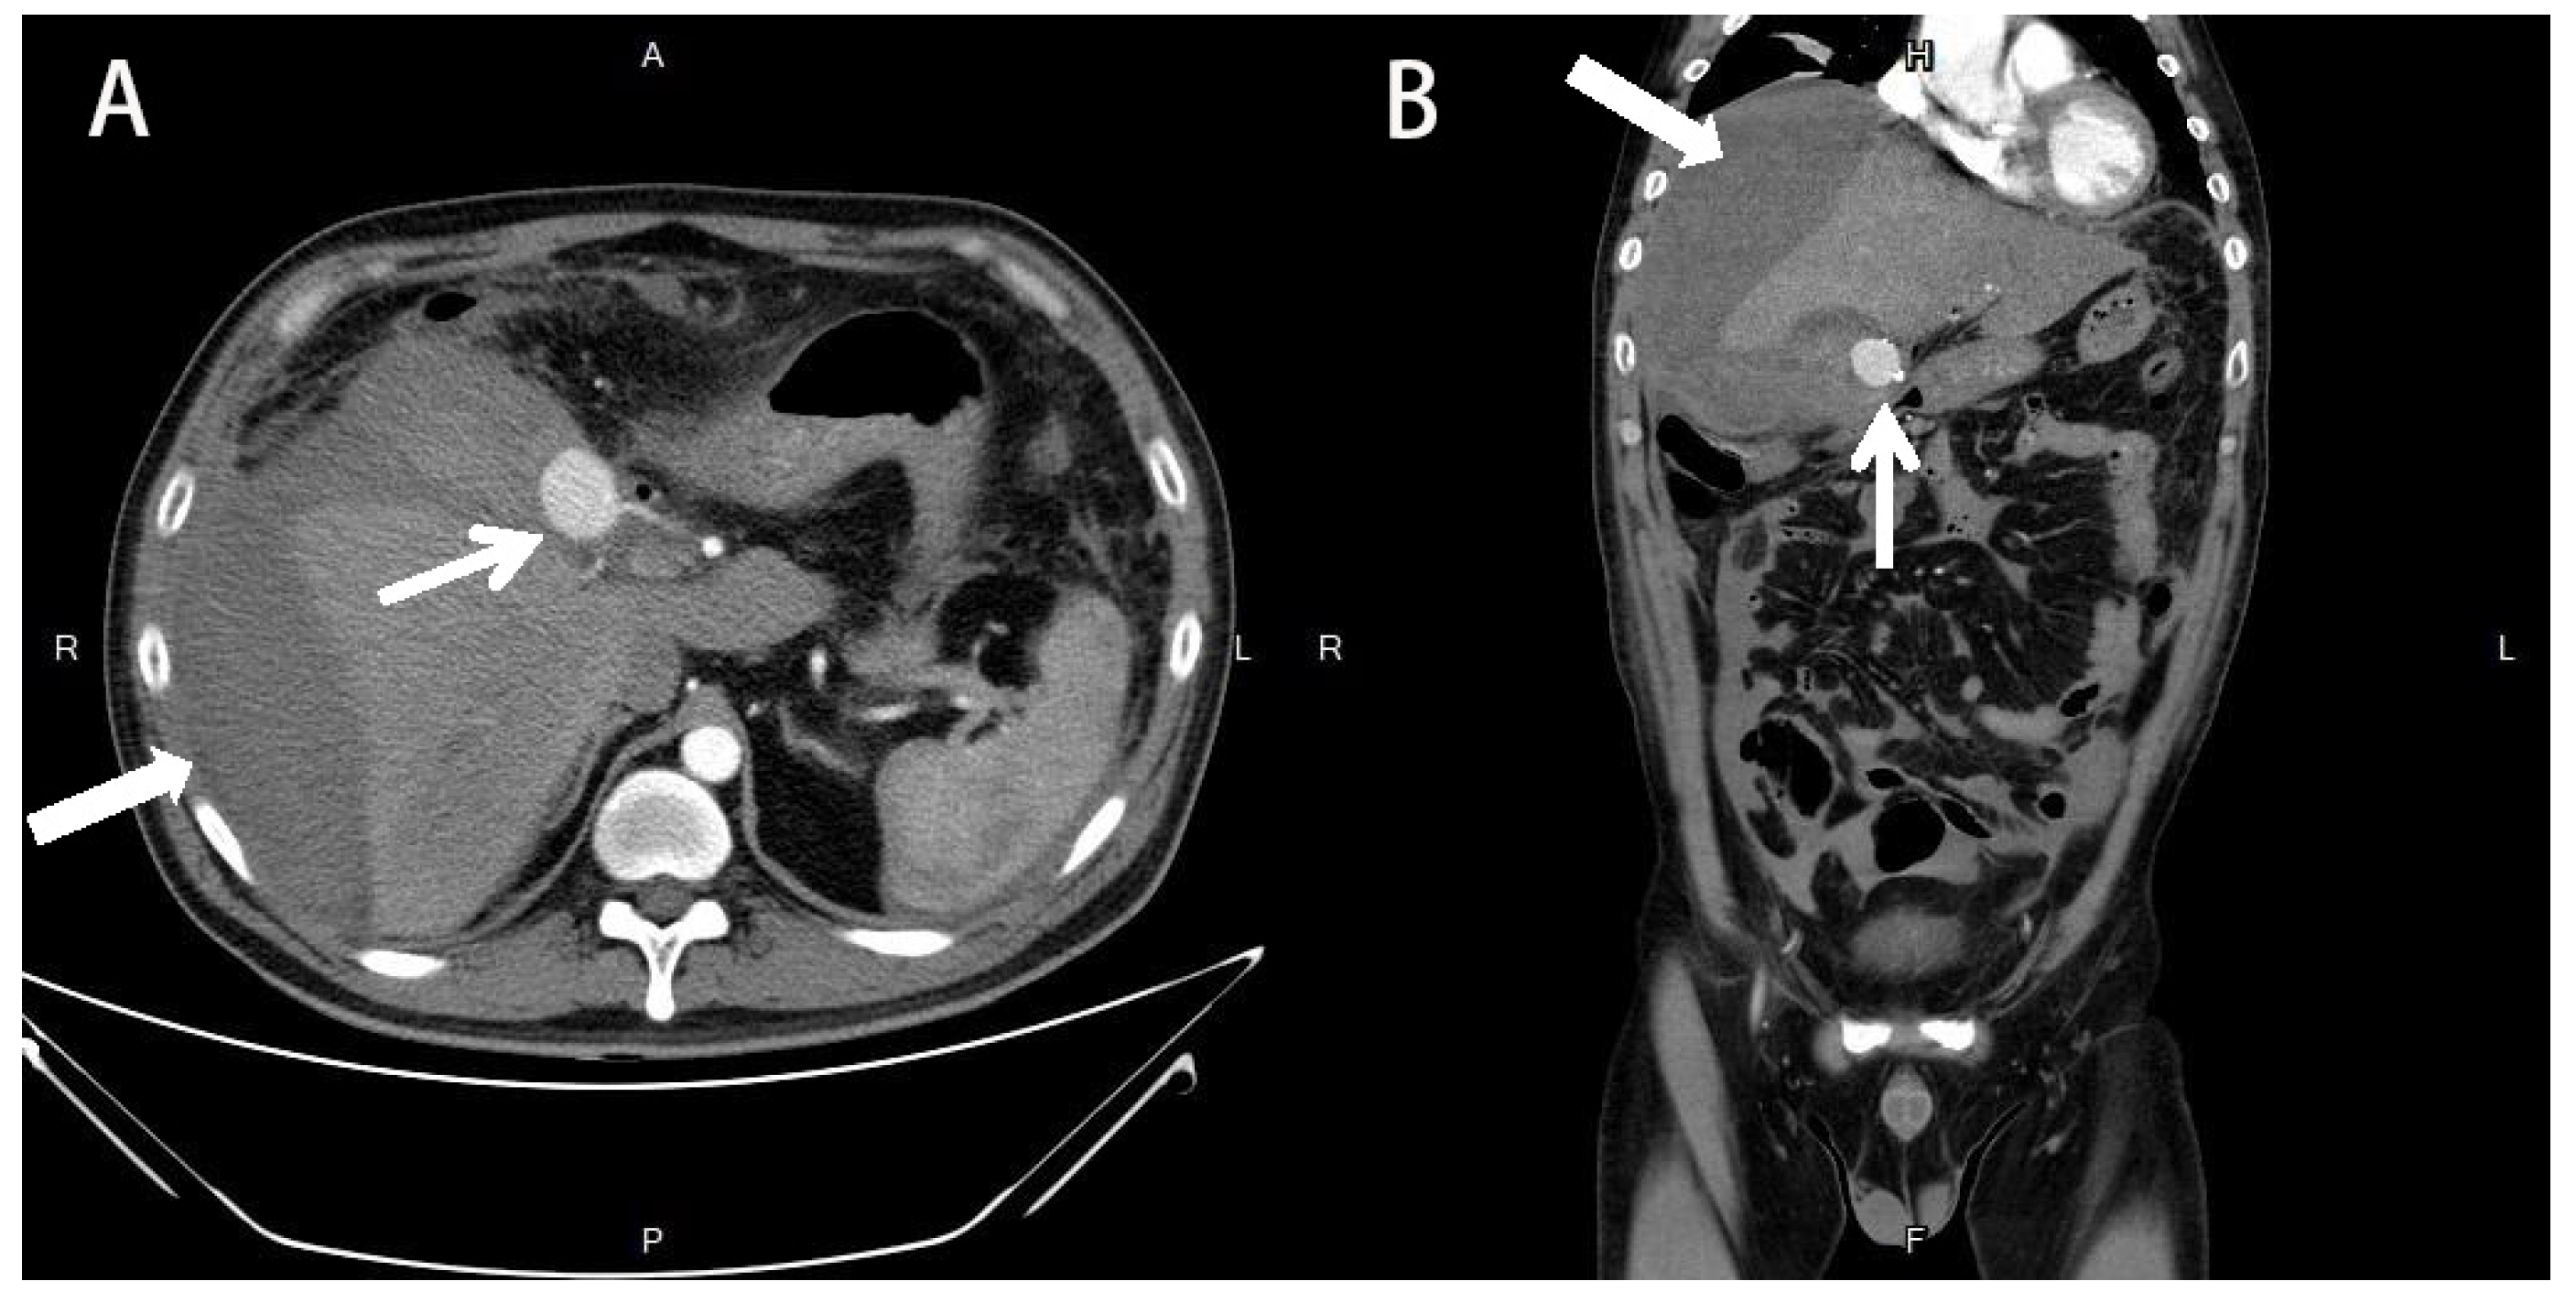

2. Detailed Case Description